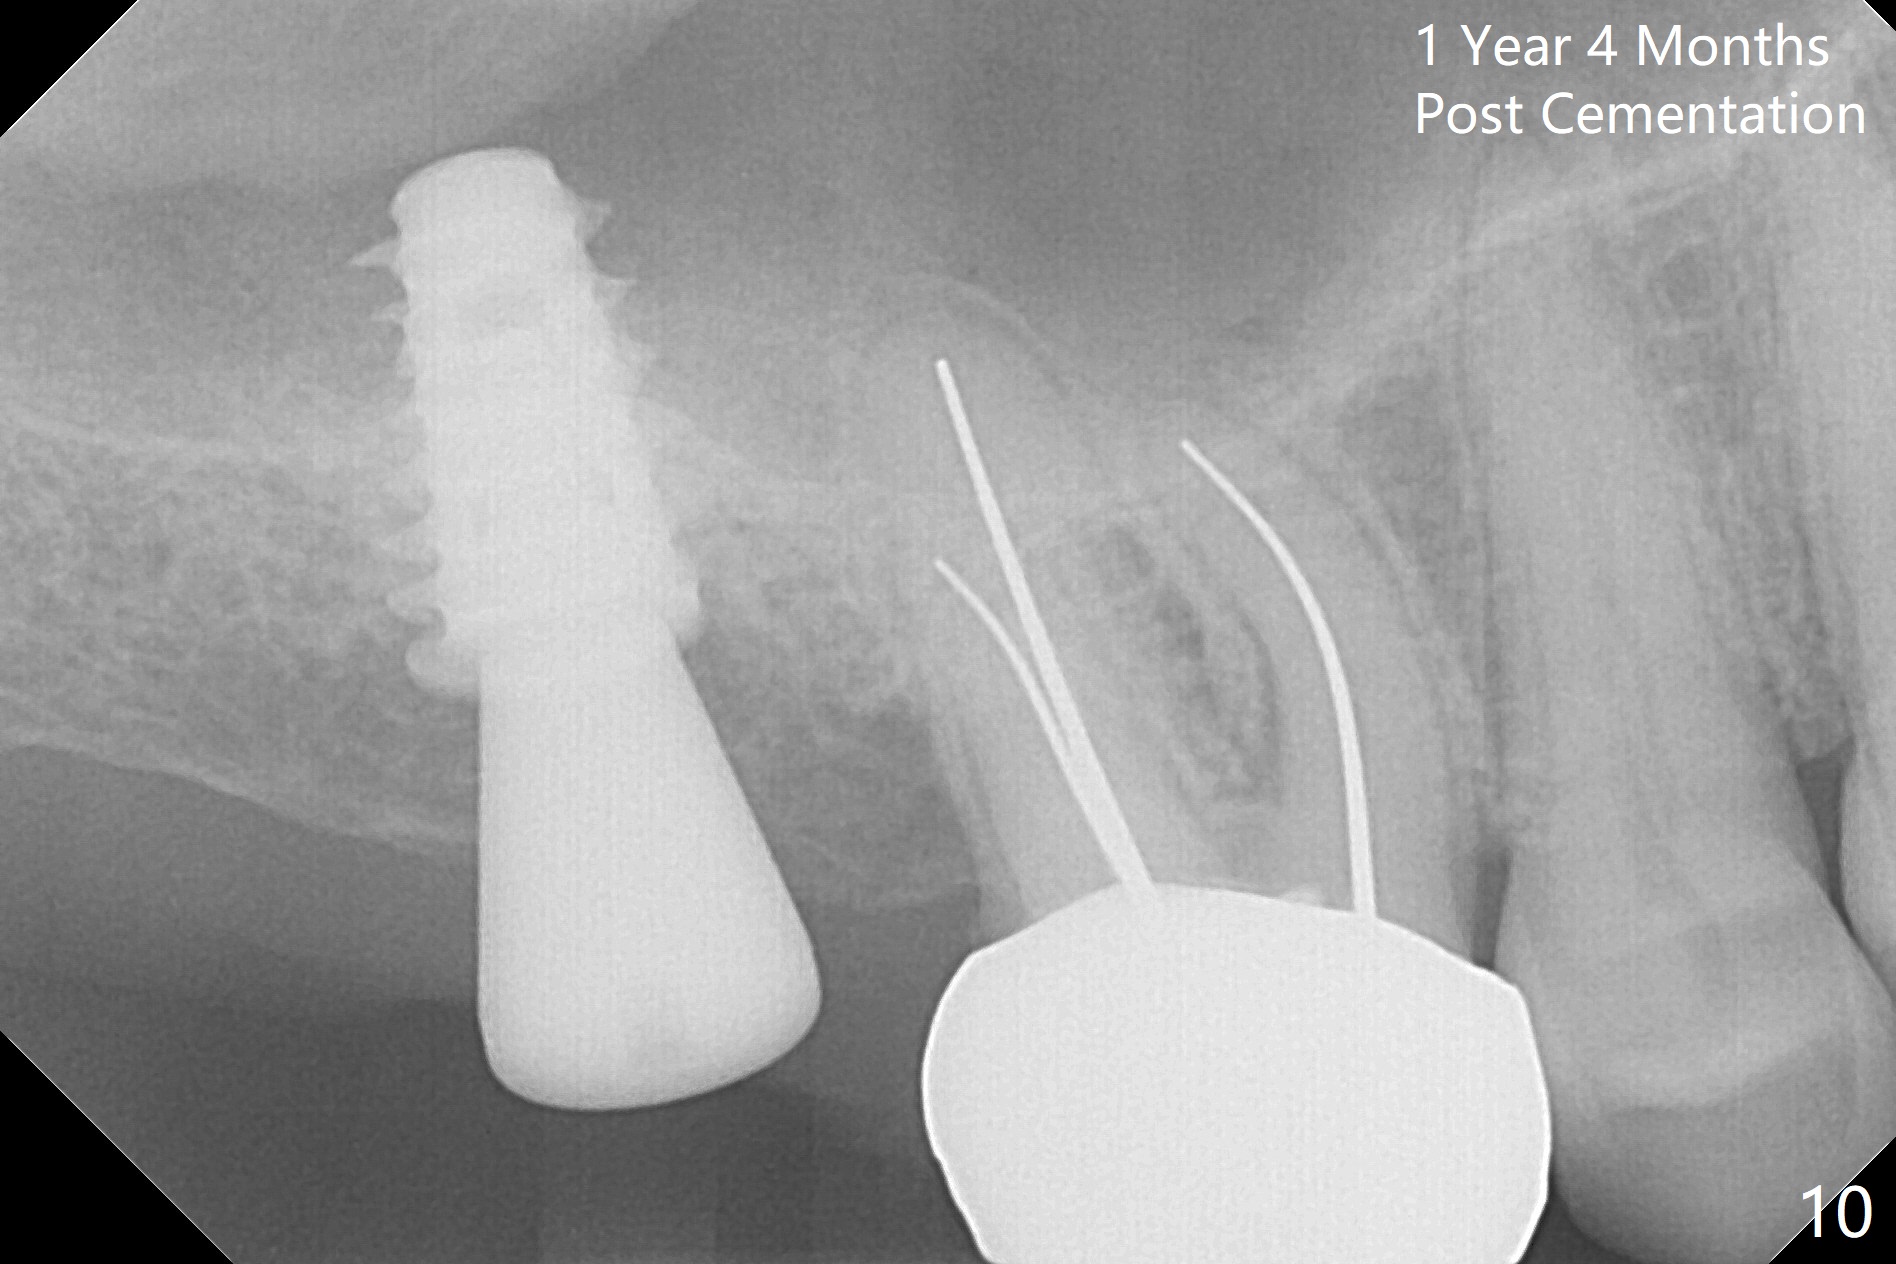

Since the ridge is wide at the site of #2, Magic Split is used for access (flapless) and bone expansion. The bone is so soft that there is no resistance until 4.3 mm Magic Expander is used for 9 mm (Fig.6). A 5 mm tap drill is stable (Fig.1), so are a 5.5x9 mm dummy implant (Fig.2) and a 6x9 mm IBS implant (Fig.3 (<: sinus lift)). In fact the distal thread is still supracrestal (Fig.4 (BW)). After additional 2 mm placement, the distal thread is subcrestal (Fig.5); the mesial margin of a 6.5x4(4) mm abutment is subgingival. A longer cuff (5 mm instead of 4 mm) is more favorable for future restoration. At present the abutment (Fig.7) as well as the tooth #3 with rugged surfaces is used to hold periodontal dressing in place. The abutment margin is completely subgingival 3 months postop (Fig.8 (white dashed line: gingival margin)). It appears that the implant is placed ~ 1 mm deeper than ideal (Fig.9). Diode laser is used for gingivectomy prior to impression. The abutment screw becomes loose 2 months post cementation. After retightening, occlusal equilibrium is conducted with 3 layers of articulating paper. Night guard is provided. The crown/abutment dislodges 1 year 2 months later. Since the gingiva is erythematous, a 6x7 mm healing abutment is placed (Fig.10). The implant seems to have been placed too deep and palatal. It appears that an abutment driver should be buried to prevent the screw re-loosening. Guided surgery should have been done.